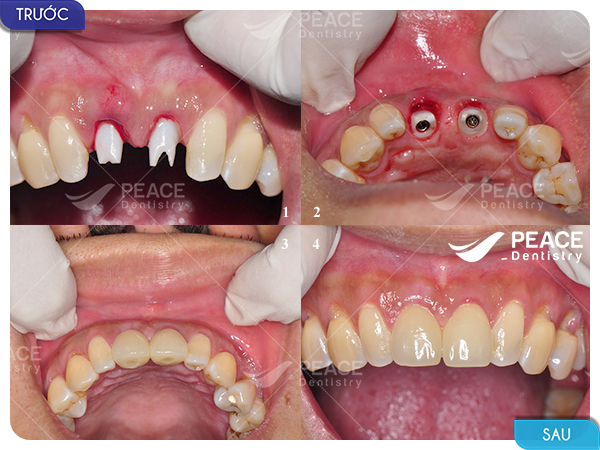

Hình ảnh thực tế